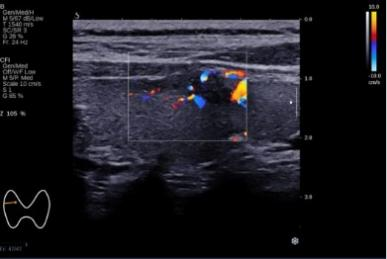

血流信号:血流信号反应结节内部或周边的血管分布情况,良恶性结节均可能出现血流信号,但恶性结节更易表现为异常血流模式改变,如血流分布紊乱,内部血流为主,高速。高阻力等。但血流信号需结合其他结节其余特征综合判断该结节是否为良恶性。

患者甲状腺彩超图像